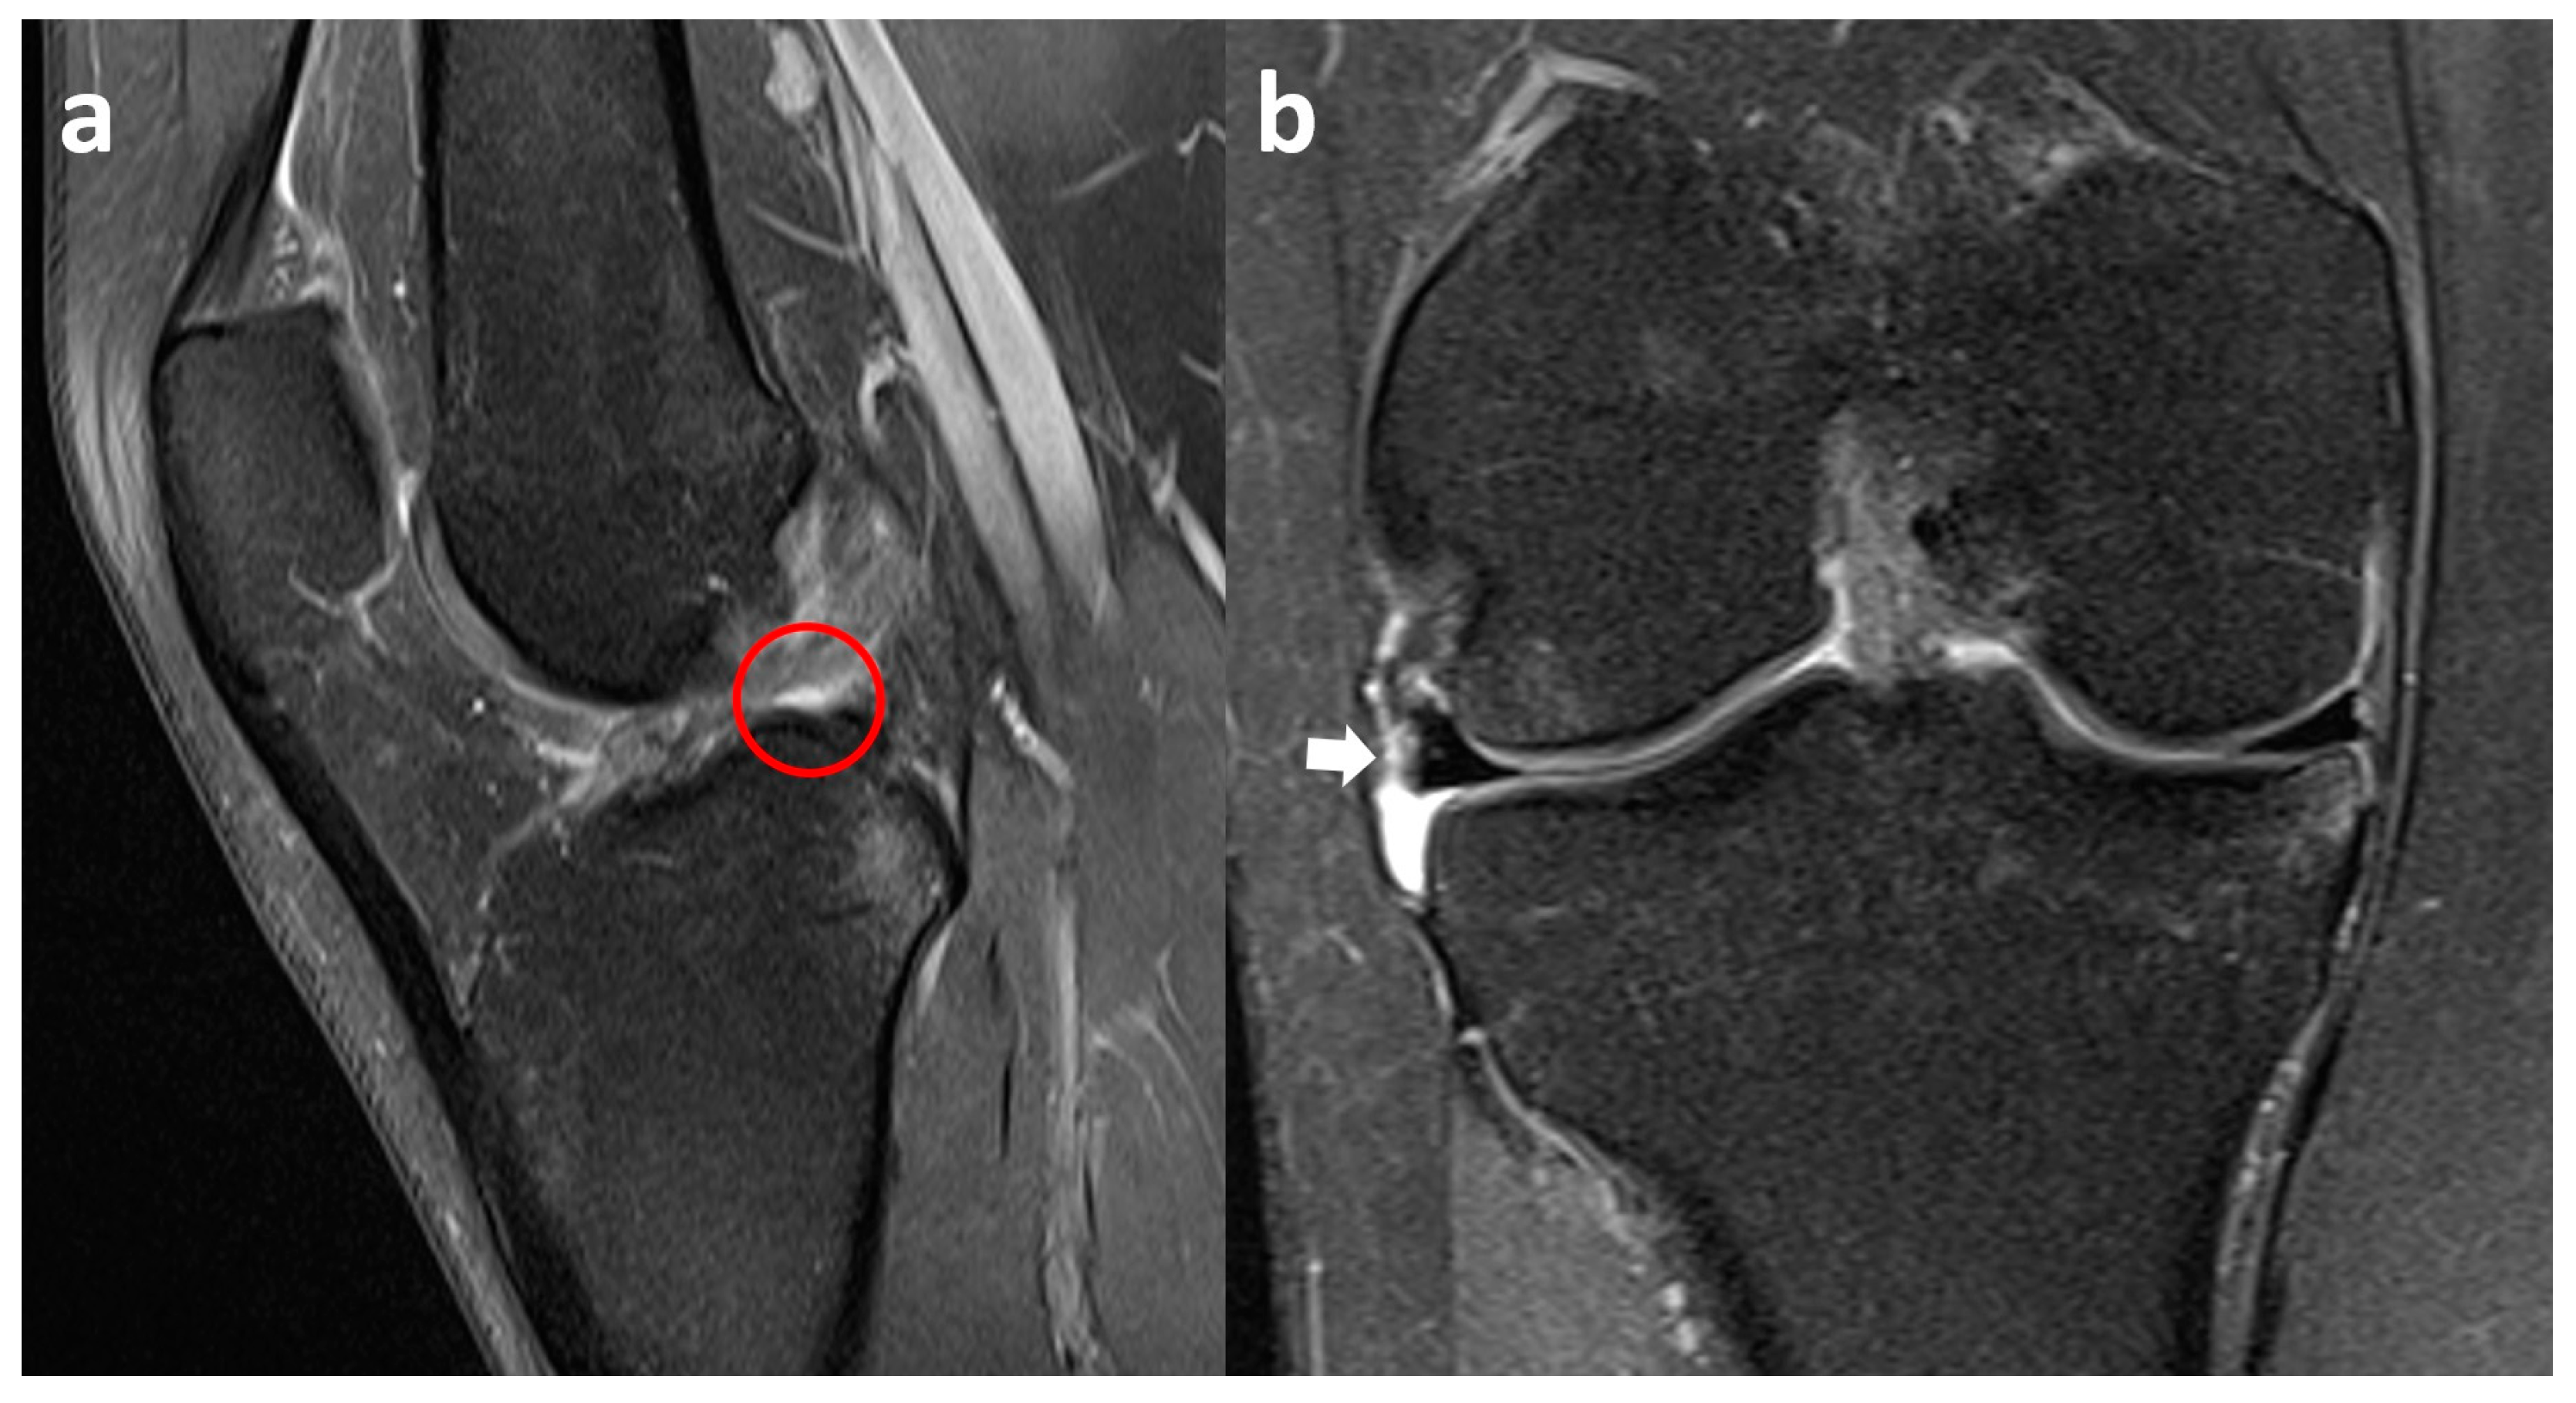

3.4. Lateral Meniscus Flap in Popliteus Recess

3.5. Lateral Meniscus Flipped in the Lateral Gutter